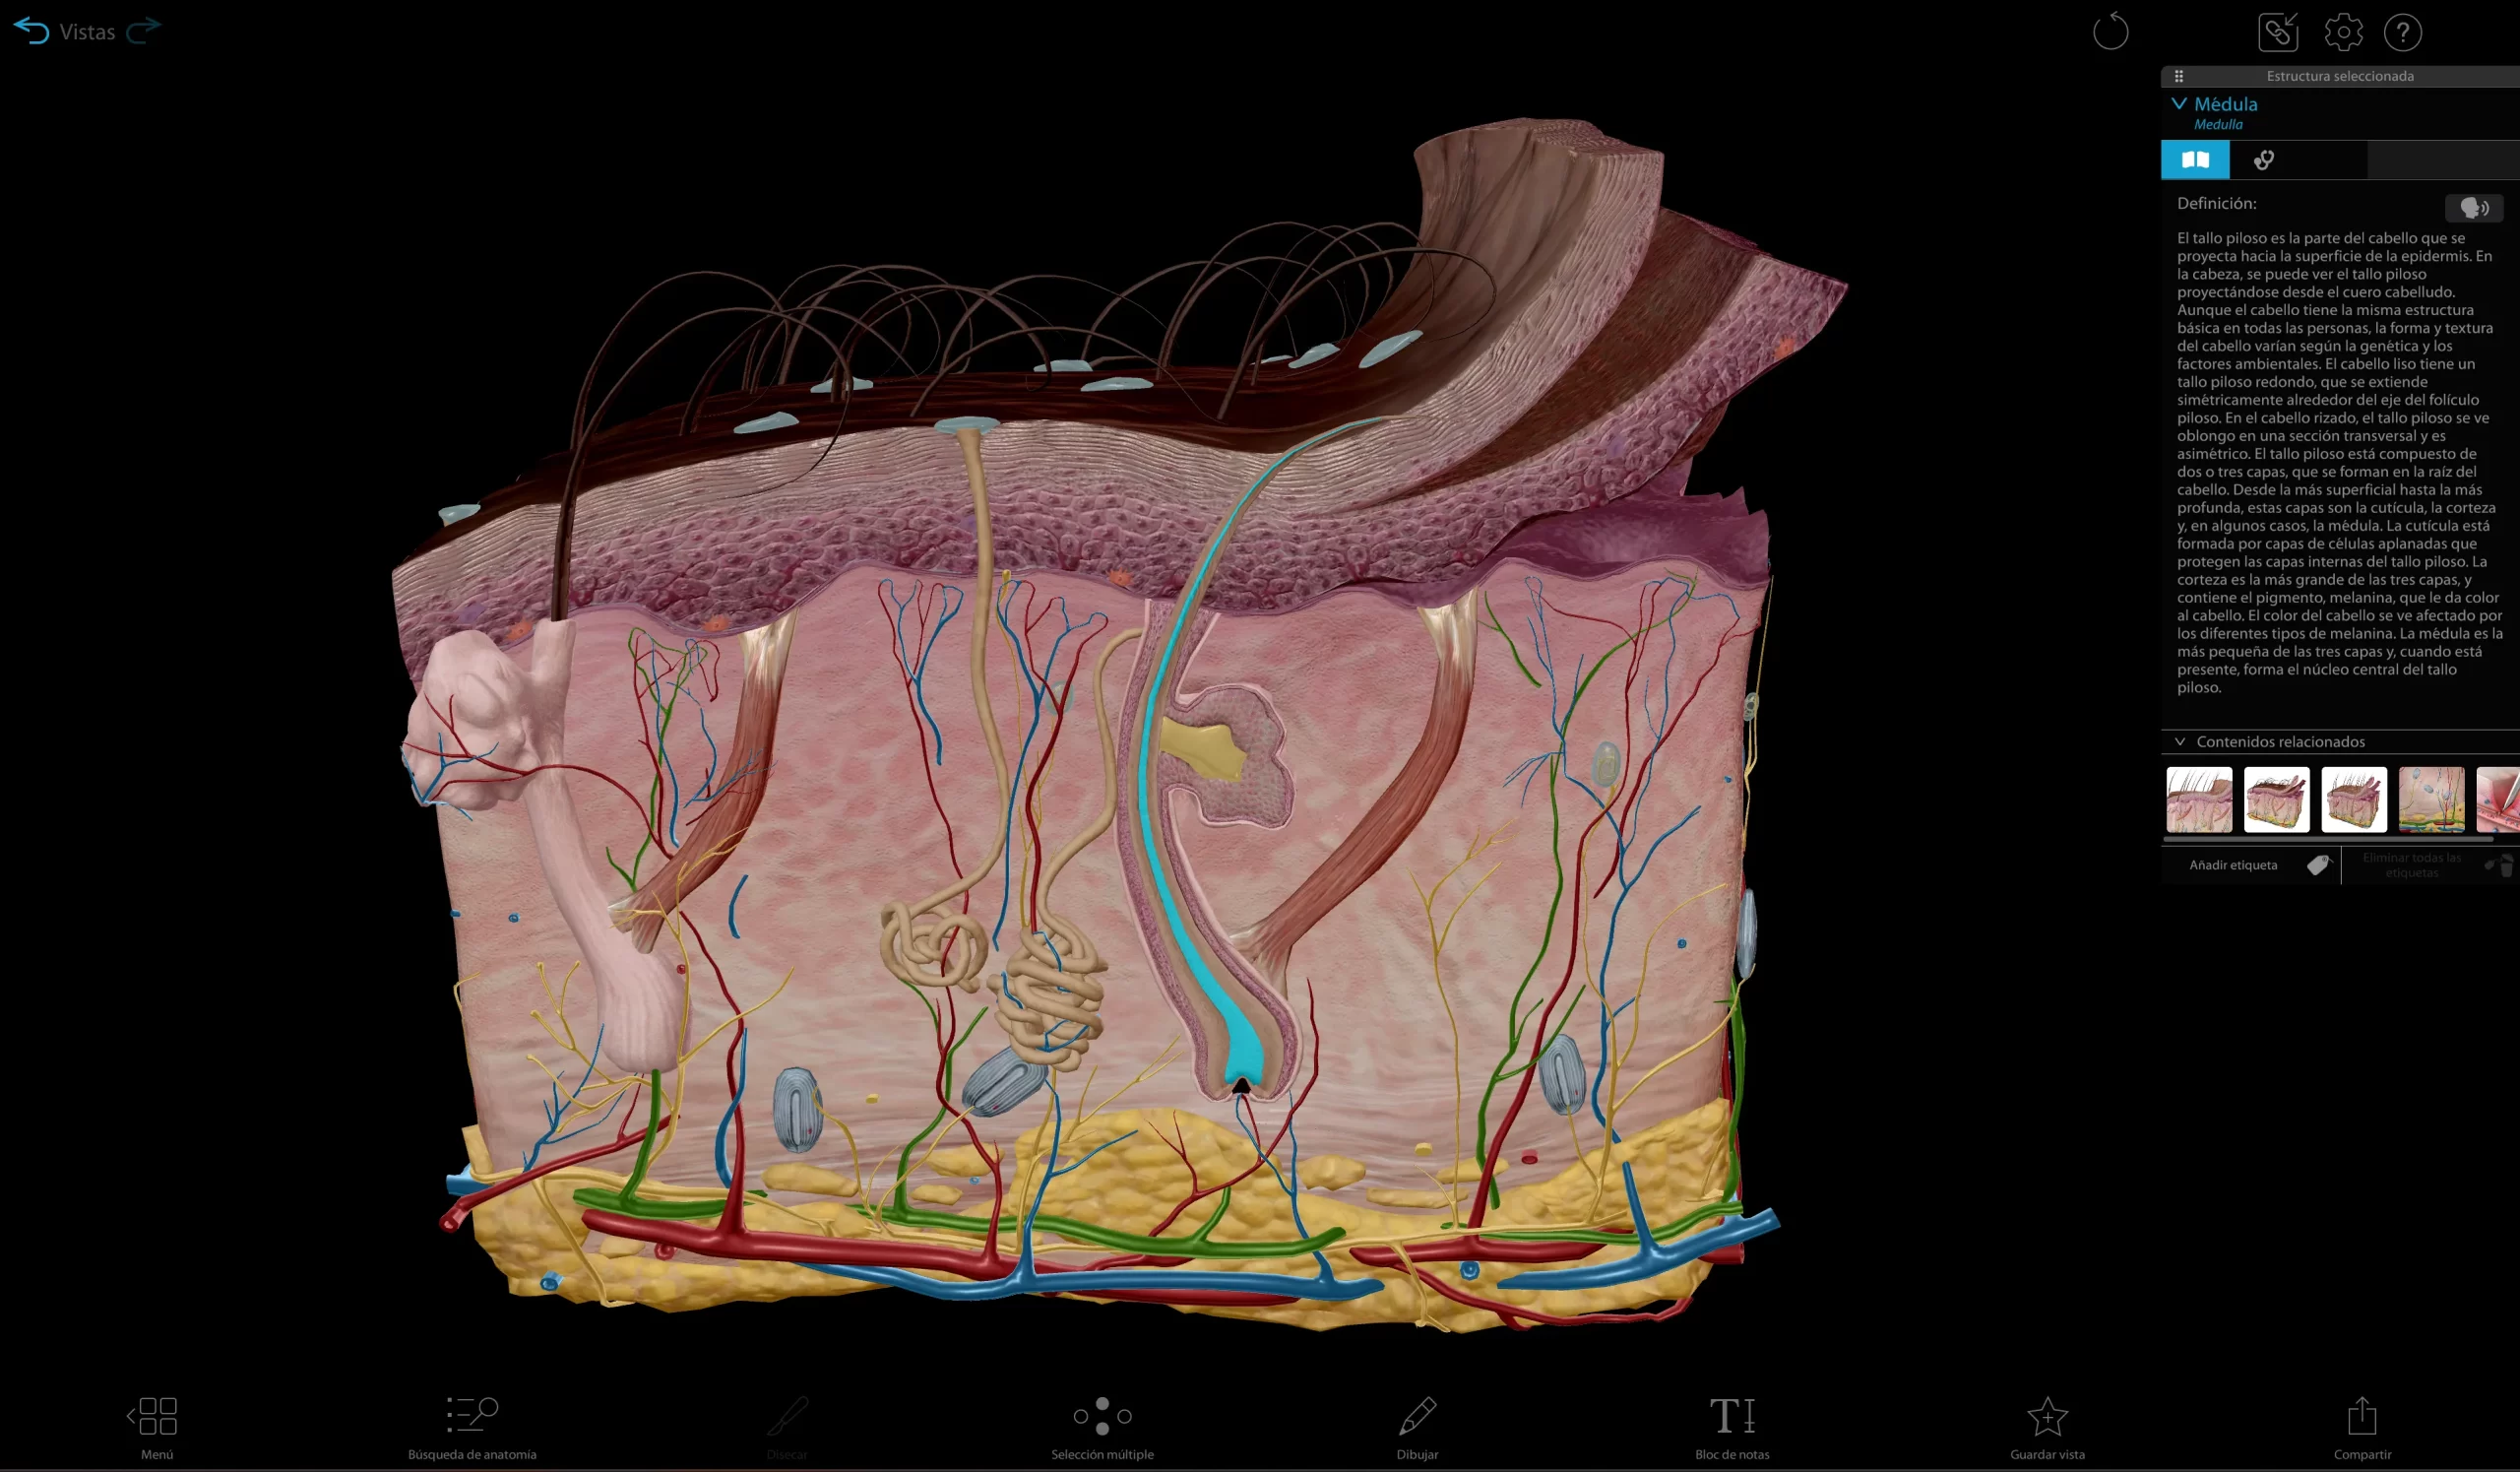

SIT Anatomy

La mesa SIT Anatomy es una solución versátil de alta tecnología con modelos 3D basados en cadáveres reales y renderizados foto realísticamente. Ofrece:

Exploración detallada de la anatomía humana y veterinaria

Herramientas interactivas de disección virtual

Visualización de imágenes DICOM y PACS

Estudio morfofuncional con correlación clínica

Ideal para facultades de Medicina, Enfermería, Fisioterapia, Veterinaria y Odontología.